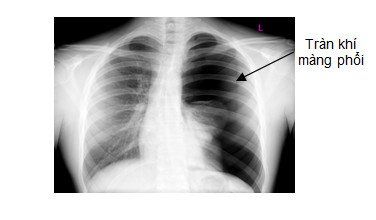

Hình tràn khí màng phổi:

Hình sáng thường ở ngoại vi và trên cao của phế trường, không thấy vân phổi, có giới hạn với nhu mô phổi là đường bờ của phế mạc tạng. Nhu mô phổi bị đẩy về phía rốn phổi (xẹp phổi bị động). Gây hiệu ứng đẩy tùy mức độ (đẩy trung thất sang bên phổi lành, giãn khoang gian sườn,...).